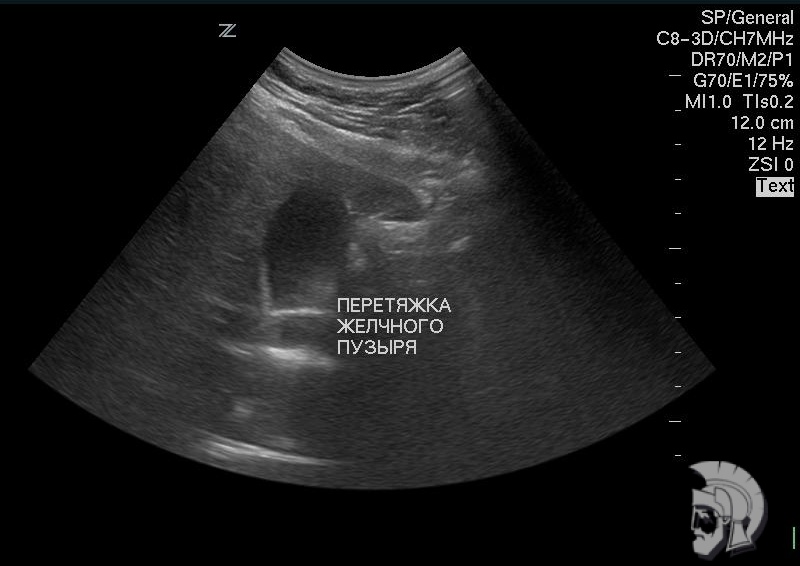

| Фото желчного пузыря. Желчный пузырь с перетяжкой у мужчины 28 лет. Желчный пузырь определяется в виде «тёмного» образования S - образной формы. Перетяжка определяется на границе средней и нижней третей желчного пузыря в виде выступающей «светлой» полоски |

Обратите внимание на совершенное качество фотографий, свидетельствующих об экспертном классе наших аппаратов УЗИ!

Использование ультразвуковых аппаратов экспертного класса с режимами энергетического ДОППЛЕРа и цветового допплера позволяет врачам Курортной клиники мужского здоровья выявлять патологические изменения на ранних этапах.